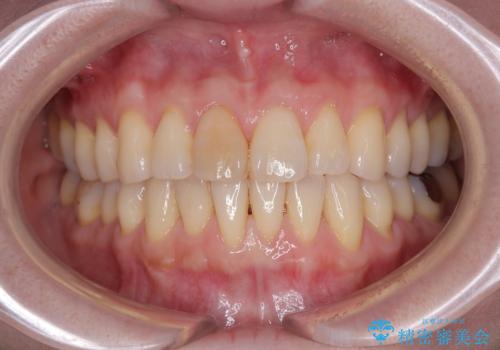

前歯のデコボコをインビザライン・モデレートで矯正治療

- 上下前歯のデコボコを気にして来院された患者様です。

安価なインビザラインパッケージを用いての治療を希望されており、デコボコの程度が中等度であったため、インビザライン・モデレートを用いて矯正治療を行うこととしました。